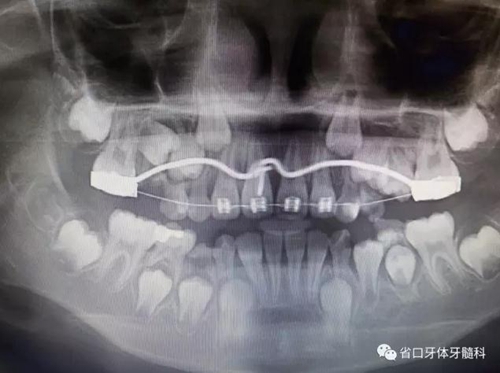

X線檢查:全景片

CBCT顯示右上中切牙埋伏阻生,牙軸呈水平位,冠向唇側(cè)、

根向腭側(cè),與鄰牙成90°夾角,牙根尚未發(fā)育完成,根端輕微彎曲。

診斷:11水平埋伏阻生。